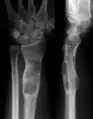

| X-ray image showing enchondromas localized in the lower part of the radius of a 7-year-old girl with Ollier disease. | |

X-ray showing enchondromas localized in the lower part of the radius of a 37-year-old patient affected with Ollier disease